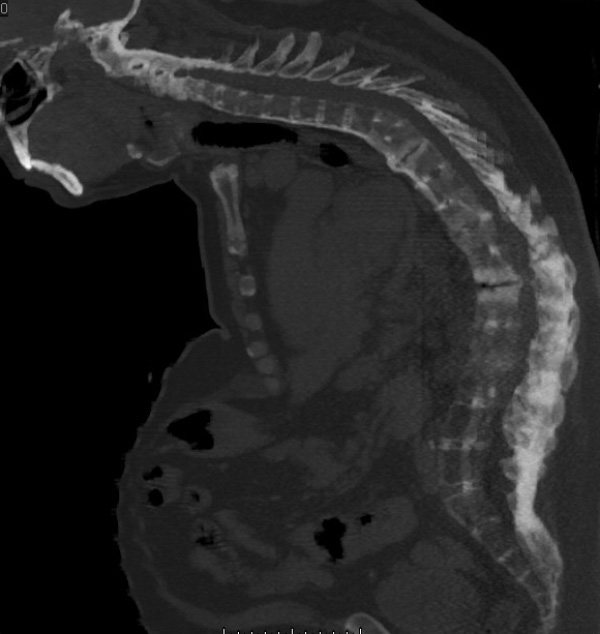

Sau đây là một số hình ảnh viêm cột sống dính khớp trên X-quang: